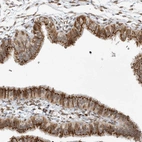

Immunohistochemical staining of human Fallopian tube shows strong granular cytoplasmic positivity in glandular cells.